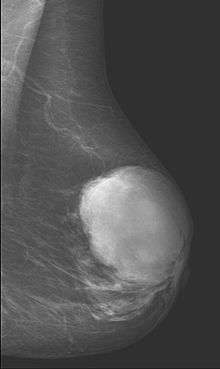

Phyllodes tumors (from Greek: phullon leaf), also cystosarcoma phyllodes, cystosarcoma phylloides and phylloides tumor, are typically large, fast-growing masses that form from the periductal stromal cells of the breast. They account for less than 1% of all breast neoplasms.

This is predominantly a tumor of adult women, with very few examples reported in adolescents. Patients typically present with a firm, palpable mass. These tumors are very fast-growing, and can increase in size in just a few weeks. Occurrence is most common between the ages of 40 and 50, prior to menopause. This is about 15 years older than the typical age of patients with fibroadenoma, a condition with which phyllodes tumors may be confused. They have been documented to occur at any age above 12 years (reference needed).